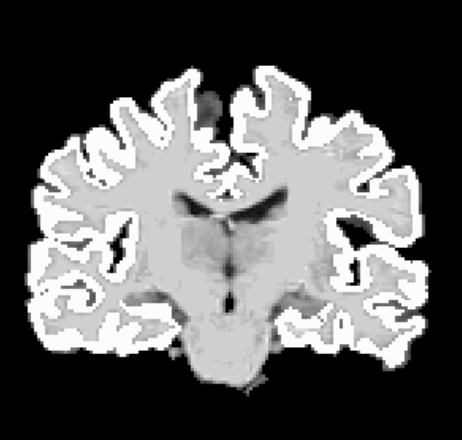

The resulting alignment is quite good (see screenshot), but it does not perform resampling of EPI to anat resampling to match anat volume resolution because I'm guessing align_epi_anat.py feeds in the '- anat2epi' option. Would appreciate it if somebody could let me know how I need to revise my afni_proc.py to align my epi2anat.

1. The reason I thought I had to align epi to anat and have it in anat resolution is because I have a gray matter mask in anat space that I want to use as is (something like in the screenshot below). Warping the gray matter mask hasn't worked out great for me, especially because I work with scans from older adults and their cortical ribbons are very thin. Would there be another way where I can use a conserved gray matter mask without having to warp epi to anat?